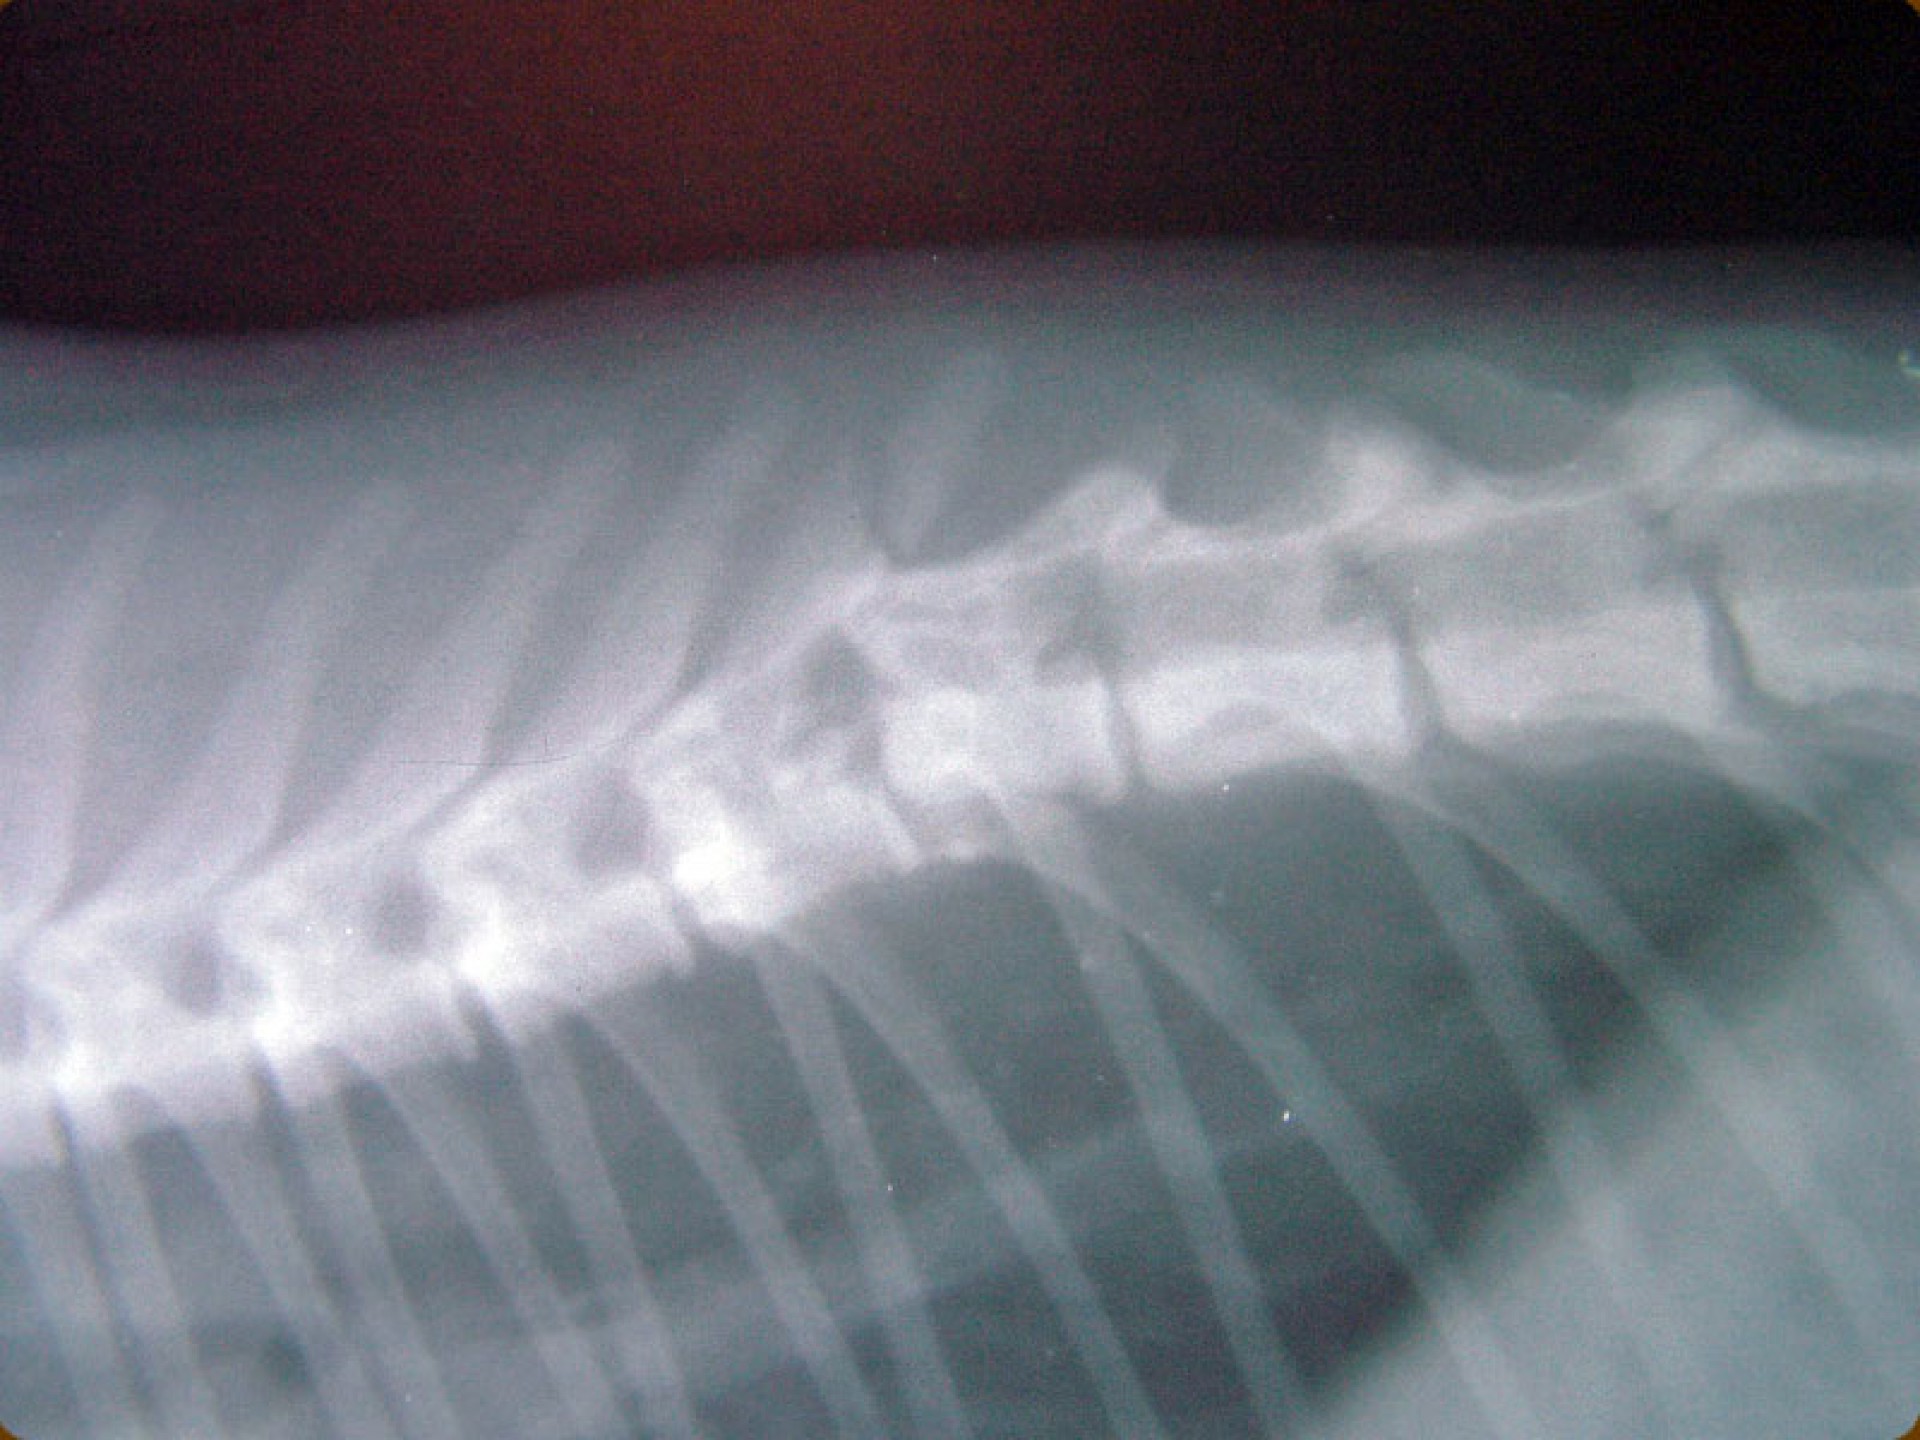

A gerinctörés diagnózisának felállítása komoly döntés elé állítja a tulajdonost és az állatorvost egyaránt. A gerinctörés következtében a gerincvelő minden esetben enyhébb-súlyosabb mértékben sérül. A gerincvelő sérülésének mértékét neurológiai vizsgálattal állapítjuk meg, de a diagnózis felállításához nélkülözhetetlen röntgen felvételről is már információt nyerhetünk a gerincvelő várható állapotáról. A tört végek egymáshoz képest történő kis mértékű elmozdulása esetén a gerincvelő körüli területek bevérzése miatt kialakult neurológiai tünetekkel találkozunk míg nagymértékű elmozdulásuk a gerincvelőt gyakorlatilag olló szerűen elnyírhatja. Így a natív röntgen felvételen a gerinccsatorna elmozdulásából már következtetést vonhatunk le a gerincvelőt ért sérülés mértékéről. A gerincvelő tényleges állapotáról azonban csak neurológiai vizsgálattal győződhetünk meg!

A gerinctörések műtéti ellátása kettős feladatot jelent: egyrészről a törés és elmozdulás következtében kialakult gerincvelő összenyomatást kell megszüntetni, másrészről a tört végeket kell adaptálni és eredeti állapotban - a további elmozdulás megakadályozása érdekében - rögzíteni. A műtéti ellátás során ezért minden esetben az érintett területen a gerinccsatorna felső csontos ívét eltávolítjuk (total laminectomia) így a gerincvelő sérülésének mértéke egyértelműen látható ill. a későbbi összenyomatása elkerülhető.

A törött csigolyatestek adaptációja és rögzítése a nyitott gerinccsatorna mellett komoly kihívást jelent. A későbbi elmozdulás elkerülésére többféle műtéttechnika alkalmazható, melyek közül a csigolyatestek lemezes osteosynthesise ill a fixateur interna használata terjedt el leginkább. Első esetben a sérülés előtti és mögötti csigolyákat lemez és csavarok segítségével egymáshoz rögzítjük, míg az utóbbi esetben a törés előtti és mögötti egy vagy több csigolyatestet két oldalról behelyezett csavarok és egy steril kétkomponensű akrilát műgyanta segítségével rögzítjük.